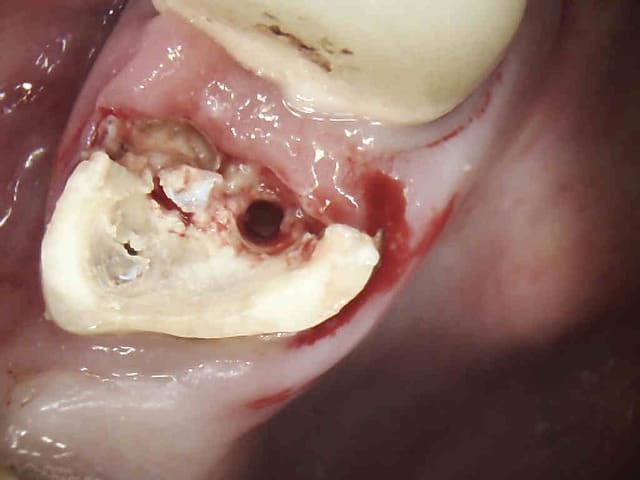

RDV d'une demi-heure initialement consult. légère gène sur 26 (tu m'étonnes). Radio de 26, anesthésie, status (antécédents de soins intensifs) detartrage, extraction. 5 mn pour le det, 2 mn pour l'extrac.

Le petit chicot au pays de la CCAM a encore frappé. -)))))